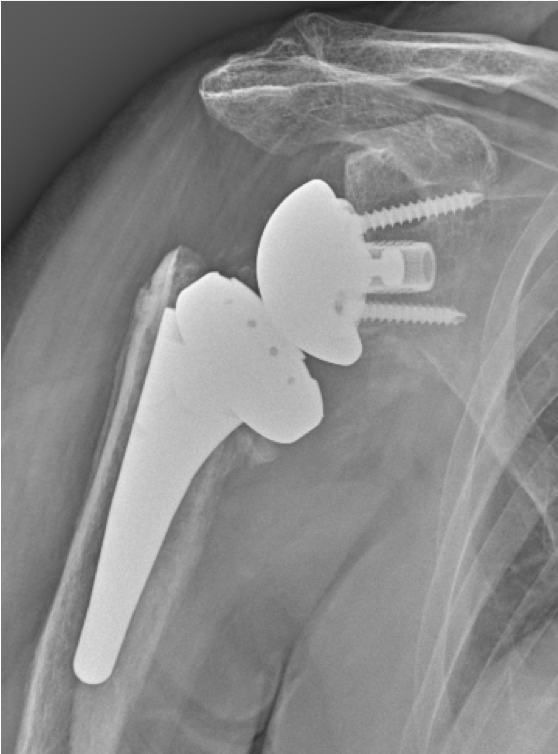

Post-op

Implantation of the LINK Embrace

- Short stem, uncemented

- Reverse Offset Tray for humerus lateralization

- Reverse Glenoid Baseplate with the TrabecuLink structure for bone integration with central and peripheral screws

- Neutral glenosphere 39 mm diameter

Result:

- Slight stem subsidence in first-follow-up

- Stabilized stem position in second follow-up

- Fracture consolidation